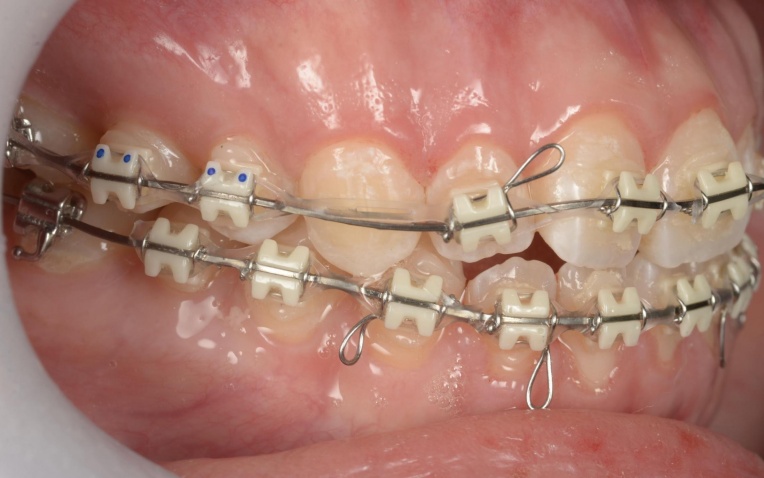

拝見したところ、重度の開咬(かいこう)が認められました。 |

| 治療内容 |

見た目と噛む機能の両方を改善するため、矯正治療を提案し、同意いただきました。 |